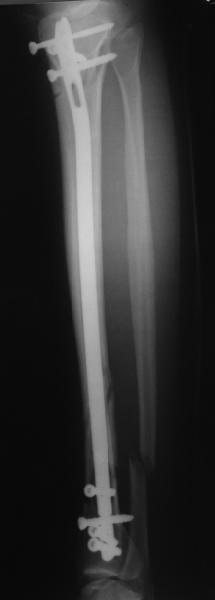

A typical case is attached, also an image with intra-op reduction obtained by a small wire distractor, in the moment of insertion a Poller wire in AP direction. Fixation by a SIGN nail. Despite the fibula was not fixed healing was obtained with the unchanged alignment.

Отправитель: Alexander Chelnokov 21 Май 2006, 23:21

I am just trying to illustrate that prevention of 1)tibial valgus and 2)loss of reduction can be provided without fibular plating. Small changes of conventional nailing techniques allow to maintain reduction of the tibia reliably without adjunctive fibular stabilization.

In delayed cases acute length restoration performed only in the tibia may leave the fibula shortened thus change the mortise. So it is reasonable to restore length of both bones simultaneously by distractor and fix the fibula not with open reduction and plating but just by a single perQ screw. Example attached.

Сделали все-таки стержнем. На всякий случай просверлил дополнительное проксимальное отверстие, так что получилось три 45-градусных винта.

В дистракторе провеи спиц поболше в прокисмальном отделе, чтобы не разобщить фрагменты при сгибании колена. Комментарии и критика приветствуются.

We proceeded with nailing using a small wire distractor, with few wires at the proximal end to prevent displacement with forced knee flexion. Images attached. Comments and critics are welcome.

In this particlar case 4 frontal wires were inserted in anterior and posterior aspects at both sides of proximal fracture, and fixed to a single half ring with some bend to provide compression with wire tension. Image attached.

На одной опоре, расположенной чуть дистальнее обычного, были закреплены 4 спицы, проведенные во фронтальной плоскости, по 2 в передней и задней части смежных фрагментов. Закреплены так, чтобы при их натяжении создалась компрессия. Картинка в приложении.